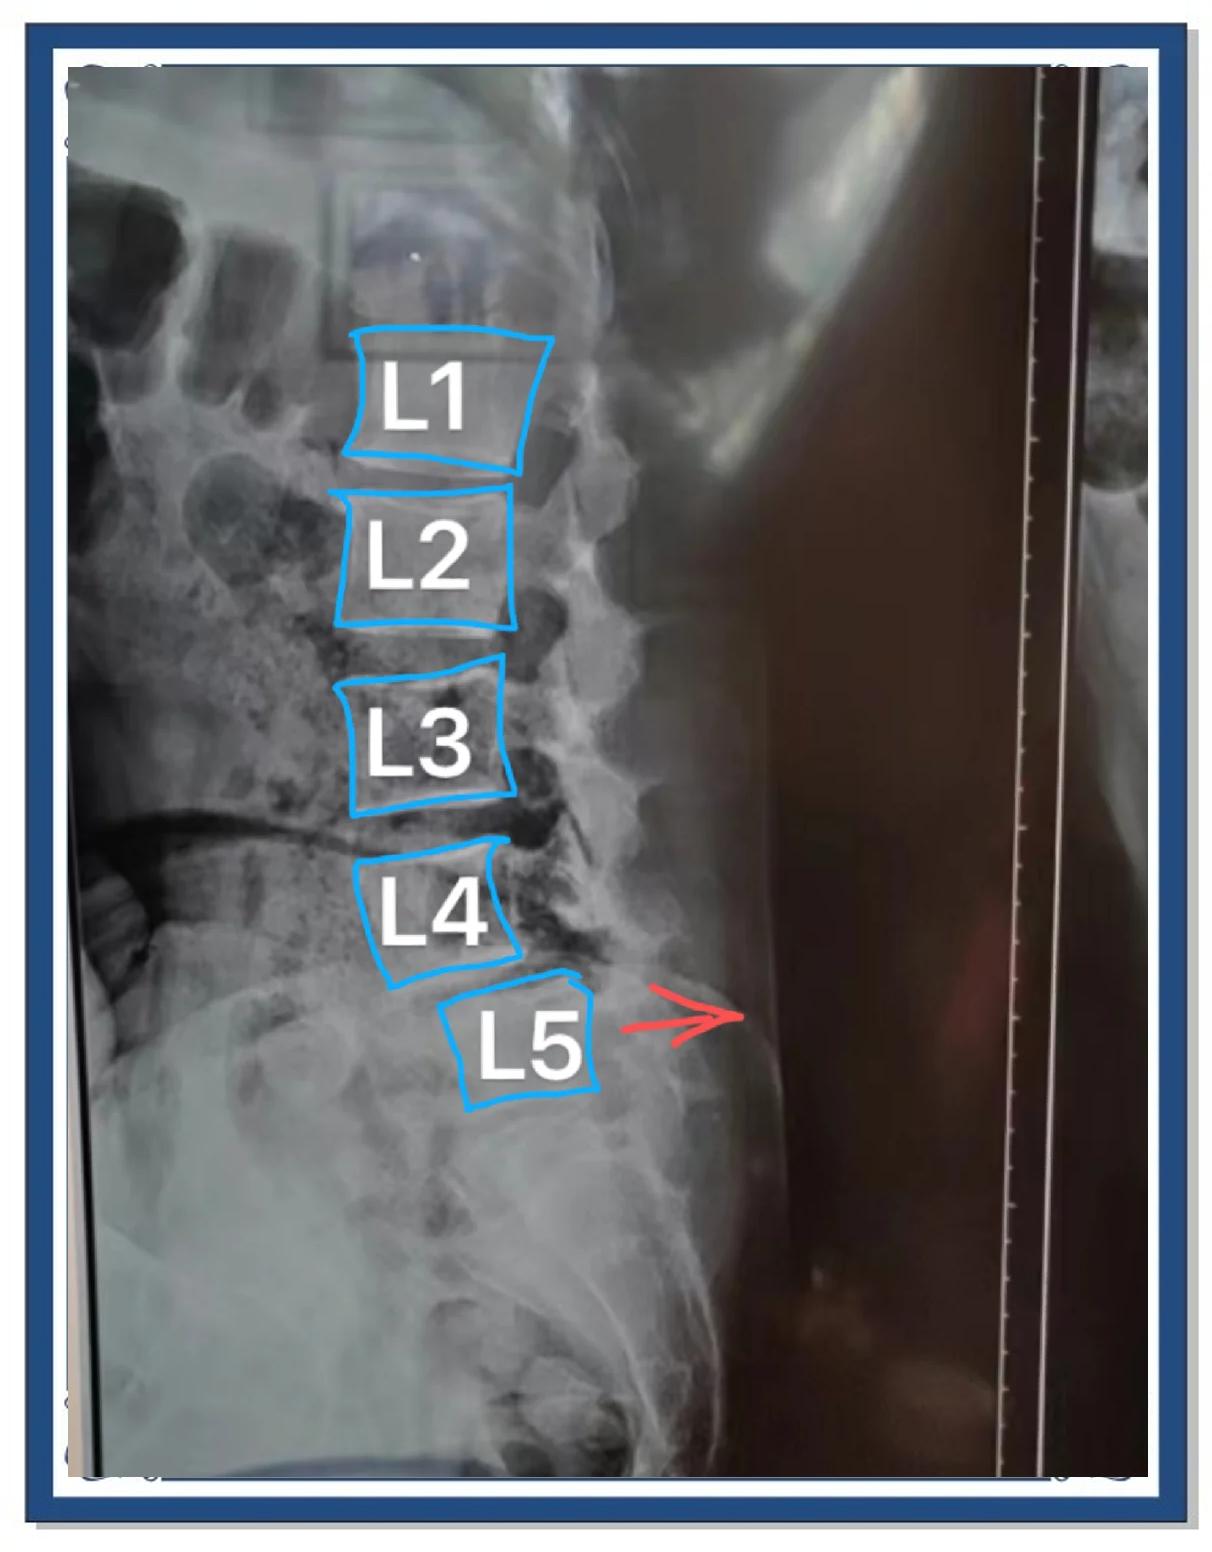

腰椎退行性变是腰椎因年龄增长或长期劳损导致的结构和功能自然衰退过程,具体表现和应对措施如下1 定义与病理基础腰椎退行性变指腰椎间盘骨质韧带等组织随年龄增长或外界因素刺激,逐渐发生水分流失弹性下降结构磨损等改变典型病理变化包括椎间盘退变纤维环破裂髓核脱水骨质增生骨赘。

腰椎退行性变是指腰椎结构与功能随年龄增长或长期应力作用发生的自然老化及适应性改变,属于骨骼系统的退行性病理过程其核心机制是腰椎间盘关节突关节韧带等结构的代谢失衡椎间盘退变是主要表现髓核水分减少导致弹性下降,纤维环出现裂隙甚至破裂,引发椎间隙高度降低这一过程可能伴随椎体边缘骨赘。

腰椎退行性变是指随着年龄增长慢性劳损等因素影响,腰椎椎体椎间盘小关节等结构发生的一系列退变改变其严重程度可分为轻度和中重度,具体表现及影响如下轻度腰椎退行性变部分人无明显症状,或仅有轻微腰部酸痛不适,久坐久站后稍加重,适当休息后可缓解这种情况对日常生活影响较小,一般。